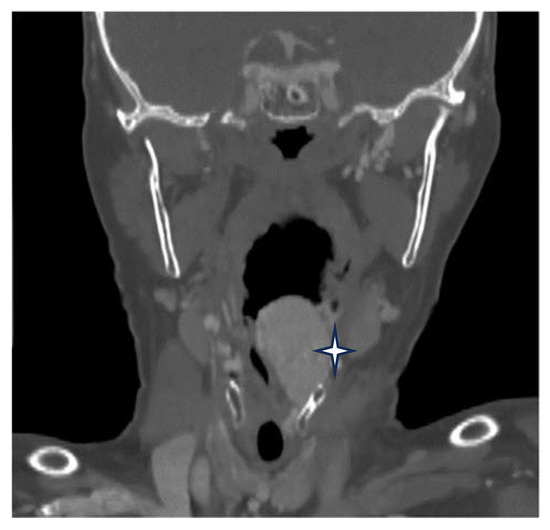

No radiotherapy was necessary because no relapse was observed at 30 days or at 3 months postoperatively (Figure 8).

Figure 8.

Postoperative view of the larynx after 3 months.

The patient did not display any breathing, phonatory, or deglutition problems. The flexible video laryngoscopy undertaken at 12 months showed us that the larynx was covered by normal mucosa, with preserved mobility of the vocal folds and no sign of relapse or any scarring postoperatively (Figure 8).